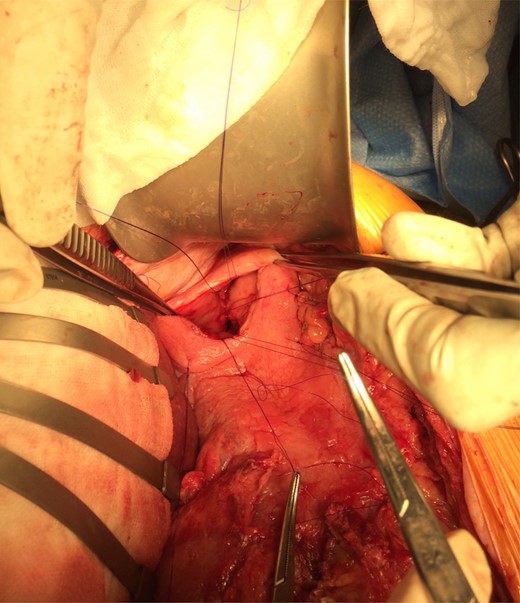

Gastroscopy the following day showed a fundal gastric ulcer and the MWT, which was now larger and deeper (Fig. 2). On Day 10, the patient underwent surgery. A midline laparotomy incision was performed, followed by extensive adhesiolysis. After the anterior wall of the stomach was exposed from the GEJ to pylorus, a longitudinal gastrotomy was created over the fundus. There was a deep MWT at GEJ extending along the greater curve of the stomach, which was bleeding actively. The MWT was oversewn with interrupted 3/0 PDS sutures and hemostasis achieved. A second, larger fundal ulcer, presumably from pressure necrosis of SB tube, was also noted. This ulcer occupied most of the fundus of stomach, which was excluded from the gastric cavity, by the closure of fundus with interrupted 3/0 PDS (Fig. 3). Postoperatively, oral fluids were commenced on Day 12. On Day 15, a Gastrografin swallow study was normal, and oral intake was encouraged. The patient recovered without complications and returned to the rehabilitation facility.

The gastric ulcer was excluded from the rest of the stomach through gastrostomy using 3/0 PDS suture.

Oversewing bleeding point of ulcer or ulcer excision are principles of surgical treatment and prevention for bleeding ulcer with the use of PPI [7]. In our case, MWT and associated ulcer was continuous and extensive and involved GEJ. Conventional surgical repair techniques seemed not feasible. The decision that a gastrectomy was deemed intolerable was due to difficult anatomy including adhesions and inflamed and fibrotic surrounding tissue, the clinical course, and the patient's compromised condition. The gastric ulcer exclusion that we performed in this case was the exclusion of ulcer internally from the gastric cavity with absorbable sutures. It was thought that hemostasis for refractory bleeding might have been achieved since it would have caused tamponade effects by itself, as well as protected from oral intake and acid production, combined with PPI.